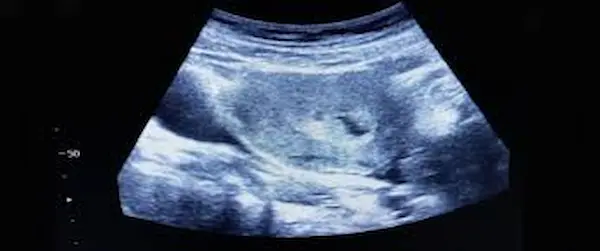

عدم نمو الجنين داخل كيس الحمل هو ما يعرف طبيًا باسم الحمل اللاجنيني أو البويضة التالفة Blighted ovum، ومعناه أن كيس الحمل يتكون داخل الرحم بشكل طبيعي في بدايته، لكن الجنين نفسه لا ينمو بداخله أو يتوقف نموه في وقت مبكر جدًا، بحيث يظهر الكيس فارغًا عند إجراء السونار، يحدث عادةً في الأسابيع الأولى من الحمل أي بين الأسبوع الخامس والعاشر.

- في الأسبوع السادس إلى الثامن حيث إنه عند عمل السونار يفترض ظهور الجنين مع النبض، وإذا كان الكيس فارغًا أو فيه كيس بدون جنين يبدأ الطبيب بالشك في الحمل اللاجنيني.

- إذا ظل الكيس فارغًا حتى الأسبوع التاسع أو العاشر بدون جنين أو نبض، يتم تشخيص الحالة بشكل شبه مؤكد.

- يعد الوسيلة الأساسية حيث يفترض رؤية الجنين وسماع نبضه، ابتداءً من الأسبوع السادس تقريبًا.

- إذا ظهر كيس الحمل فارغاً أو كان جنين بلا نبض بعد مرور الوقت الكافي، يشير ذلك إلى توقف النمو.